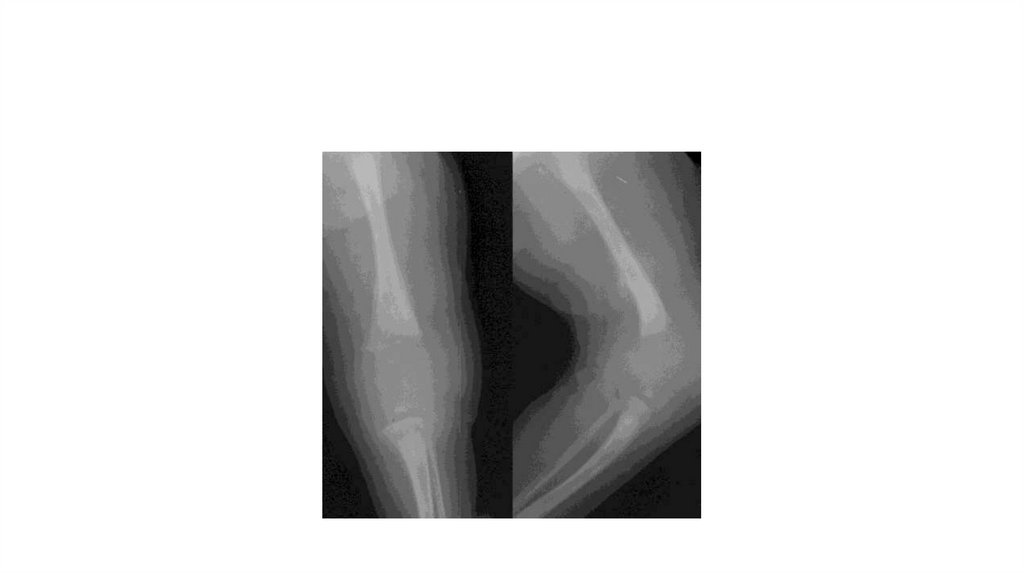

Воспалительные заболевания опорнодвигательного аппарата

заболевания опорнодвигательного аппарата»